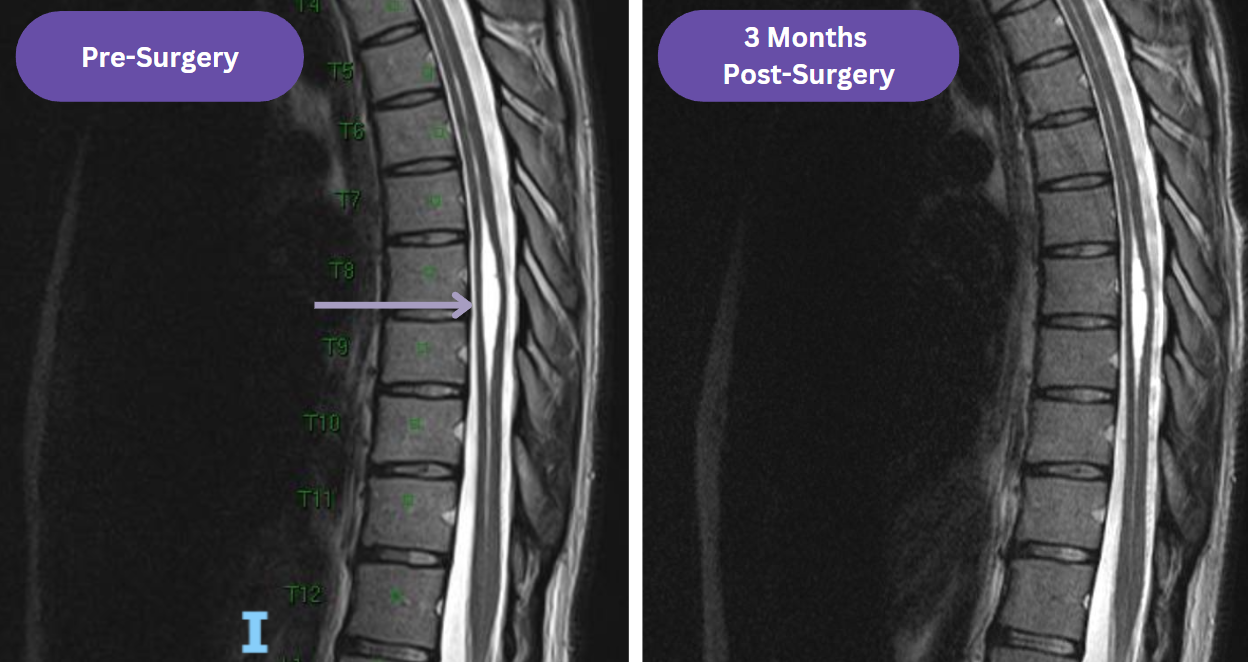

The not-horrible-but-not-amazing news: My syrinx does not look much better.

The MRI report noted there was a decrease in the width of my syrinx from 7 mm to 6 mm. But since the improvement was hard to see at first glance, I was pretty bummed. The length of my syrinx is the same as pre-surgery, extending from my cervical to my lumbar region. However, when reviewing my MRI, my doctor said that even though he wished my syrinx was smaller too, he “wouldn’t lose sleep over it,” which was very encouraging. He let me know we could still see some improvement over the next year. Since the widest part of my syrinx is so low in my thoracic spine, it could take longer to see changes. Furthermore, since I am not experiencing sensation or temperature loss in the T7 region or below, he is confident that my symptoms are not related to my syrinx, which is fantastic. So we are planning to keep monitoring if the syrinx progresses with annual physical exam and MRI.

Figure 5. Comparison of my syrinx in November 2024 versus February 2025 up close around T7-T9.